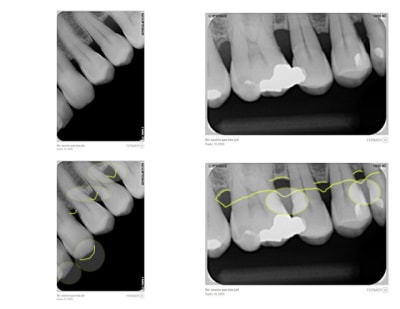

Pas de pano ? On n'a pas les même suivis , NP ( nouveau patient) = pano et radio complête.

Examen paro ? sondage et rétro ?

pour la dent 12 , il semble que ce soit lié avec la Cl-2, div-2 ( une des variante). Mais peut-être paro...on manque d'info. Pour le wax-up, c'est trop tôt.

> Examen paro ? sondage et rétro ?

pas de pano au cabinet, pas de systématisation de la pano du coup

quelques retro faites en 2009 (critiquables, je sais, ça va mieux aujourd'hui)

Voir images

On peut y voir une remodelage osseux, de tartre, l'usure de la canine

Tu as des photo en vue occlusale, haut et bas ?